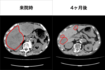

「人間ドックで左腎に6cmの腫瘍が見つかりました。ステージは1bですが、転移があればステージ4になる可能性もありました。現実を受け入れられず『医者の私ががんのはずがない』と、かたくなに受け入れられなかったですね」(船戸先生、以下同)